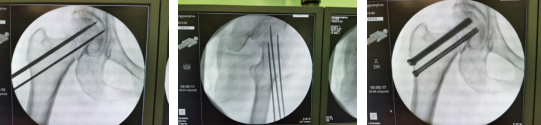

术中,先将患者置于牵引床上闭合复位,C型臂透视见骨折端对位良好;接着,机器人C型臂透视对患者股骨颈部位进行三维扫描,图像被同步传输至骨科手术机器人系统。同时,在导航系统屏幕上规划好钉道。随后,机器人的机械臂将手术工具精确定位到手术位置,套筒指向目的钉道的进钉点。手术小组沿着套筒钻入导引针,确认位置无误,再把空心加压螺钉通过导引针固定,拔出导针。

手术历时40分钟,顺利完成。创伤骨科任海东主任说,以往股骨颈骨折如何精准置钉一直是个难题,但在机器人导航辅助下,手术团队将精确度误差控制在0.2毫米以内。整个手术过程中,透视次数大幅减少,对患者及医护人员的放射保护大大增强。创口仅1厘米,患者术后几乎感觉不到疼痛。